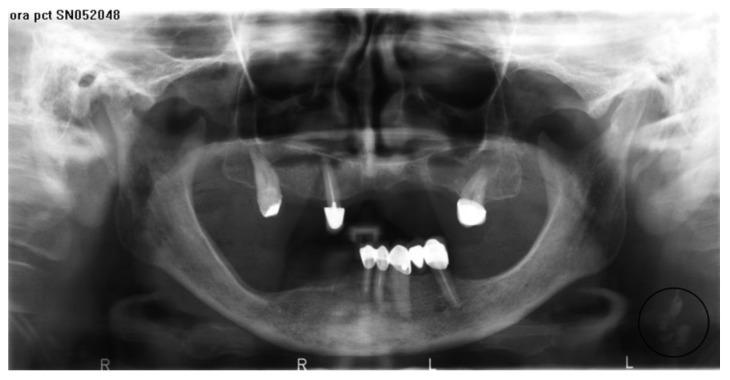

Panoramic radiographs made between 2005 and 2012 in 4000 patients born between 1922 and 1958 were accessed from the server of the Department of Radiology and analyzed for the presence or absence of CACs by a group of trained dentists.

The anatomical area covered by the analysis was visible in 2189 images (54.73%). Calcifications in the carotid arteries were found in 468 (21.68%) patients, including 327 (14.94%) unilaterally and 141 (6.44%) bilaterally. CACs were found in 284 (60.68%) women and 184 (39.32%) men.

The prevalence rate of CACs detected on panoramic radiographs in patients aged 54 and older was 21.68%, which makes it an important clinical problem.